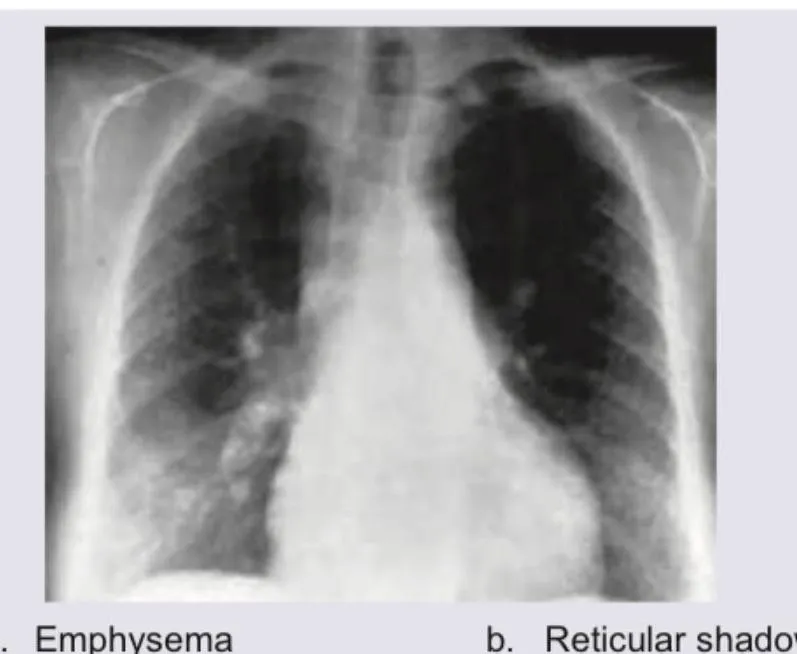

- UIP pattern: peripheral + basilar reticulation + honeycombing, no ground-glass

| IPF (UIP) | Peripheral, basilar reticulation + honeycombing | 40-60% predicted | Normal or ↑ neutrophils | UIP: fibroblastic foci | Antifibrotics 50% slow decline |